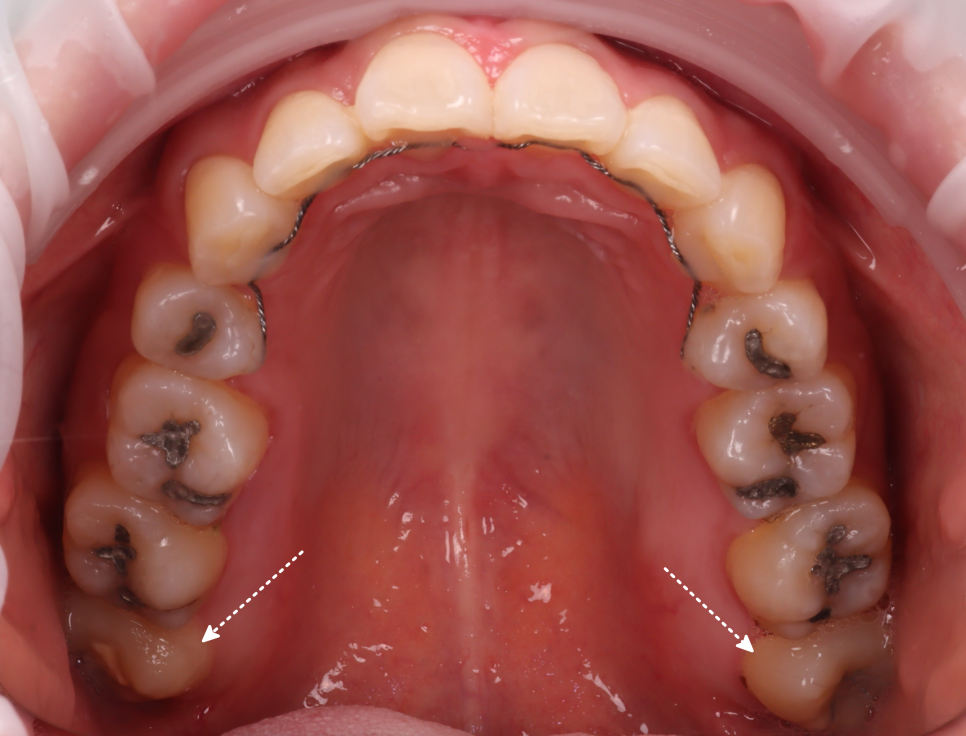

잇몸 속에 묻혀 있는 형태는 육안으로 확인하기가 힘들어서 엑스레이를 통해 정확한 상태를 확인해 봤는데요.

촬영일 : 251121

위쪽은 똑바로 나있었지만 아래 사랑니가 모두 매복 되었고 뿌리가 두 갈래로 갈라져 있었으며, 끝이 많이 휘어 있는 형태였어요.

또, 뿌리 끝과 하치조신경관의 거리가 매우 가까웠는데요.

이런 경우, 발치하다가 하치조신경관이 손상되는 경우도 있어서 매우 조심해야 됩니다.